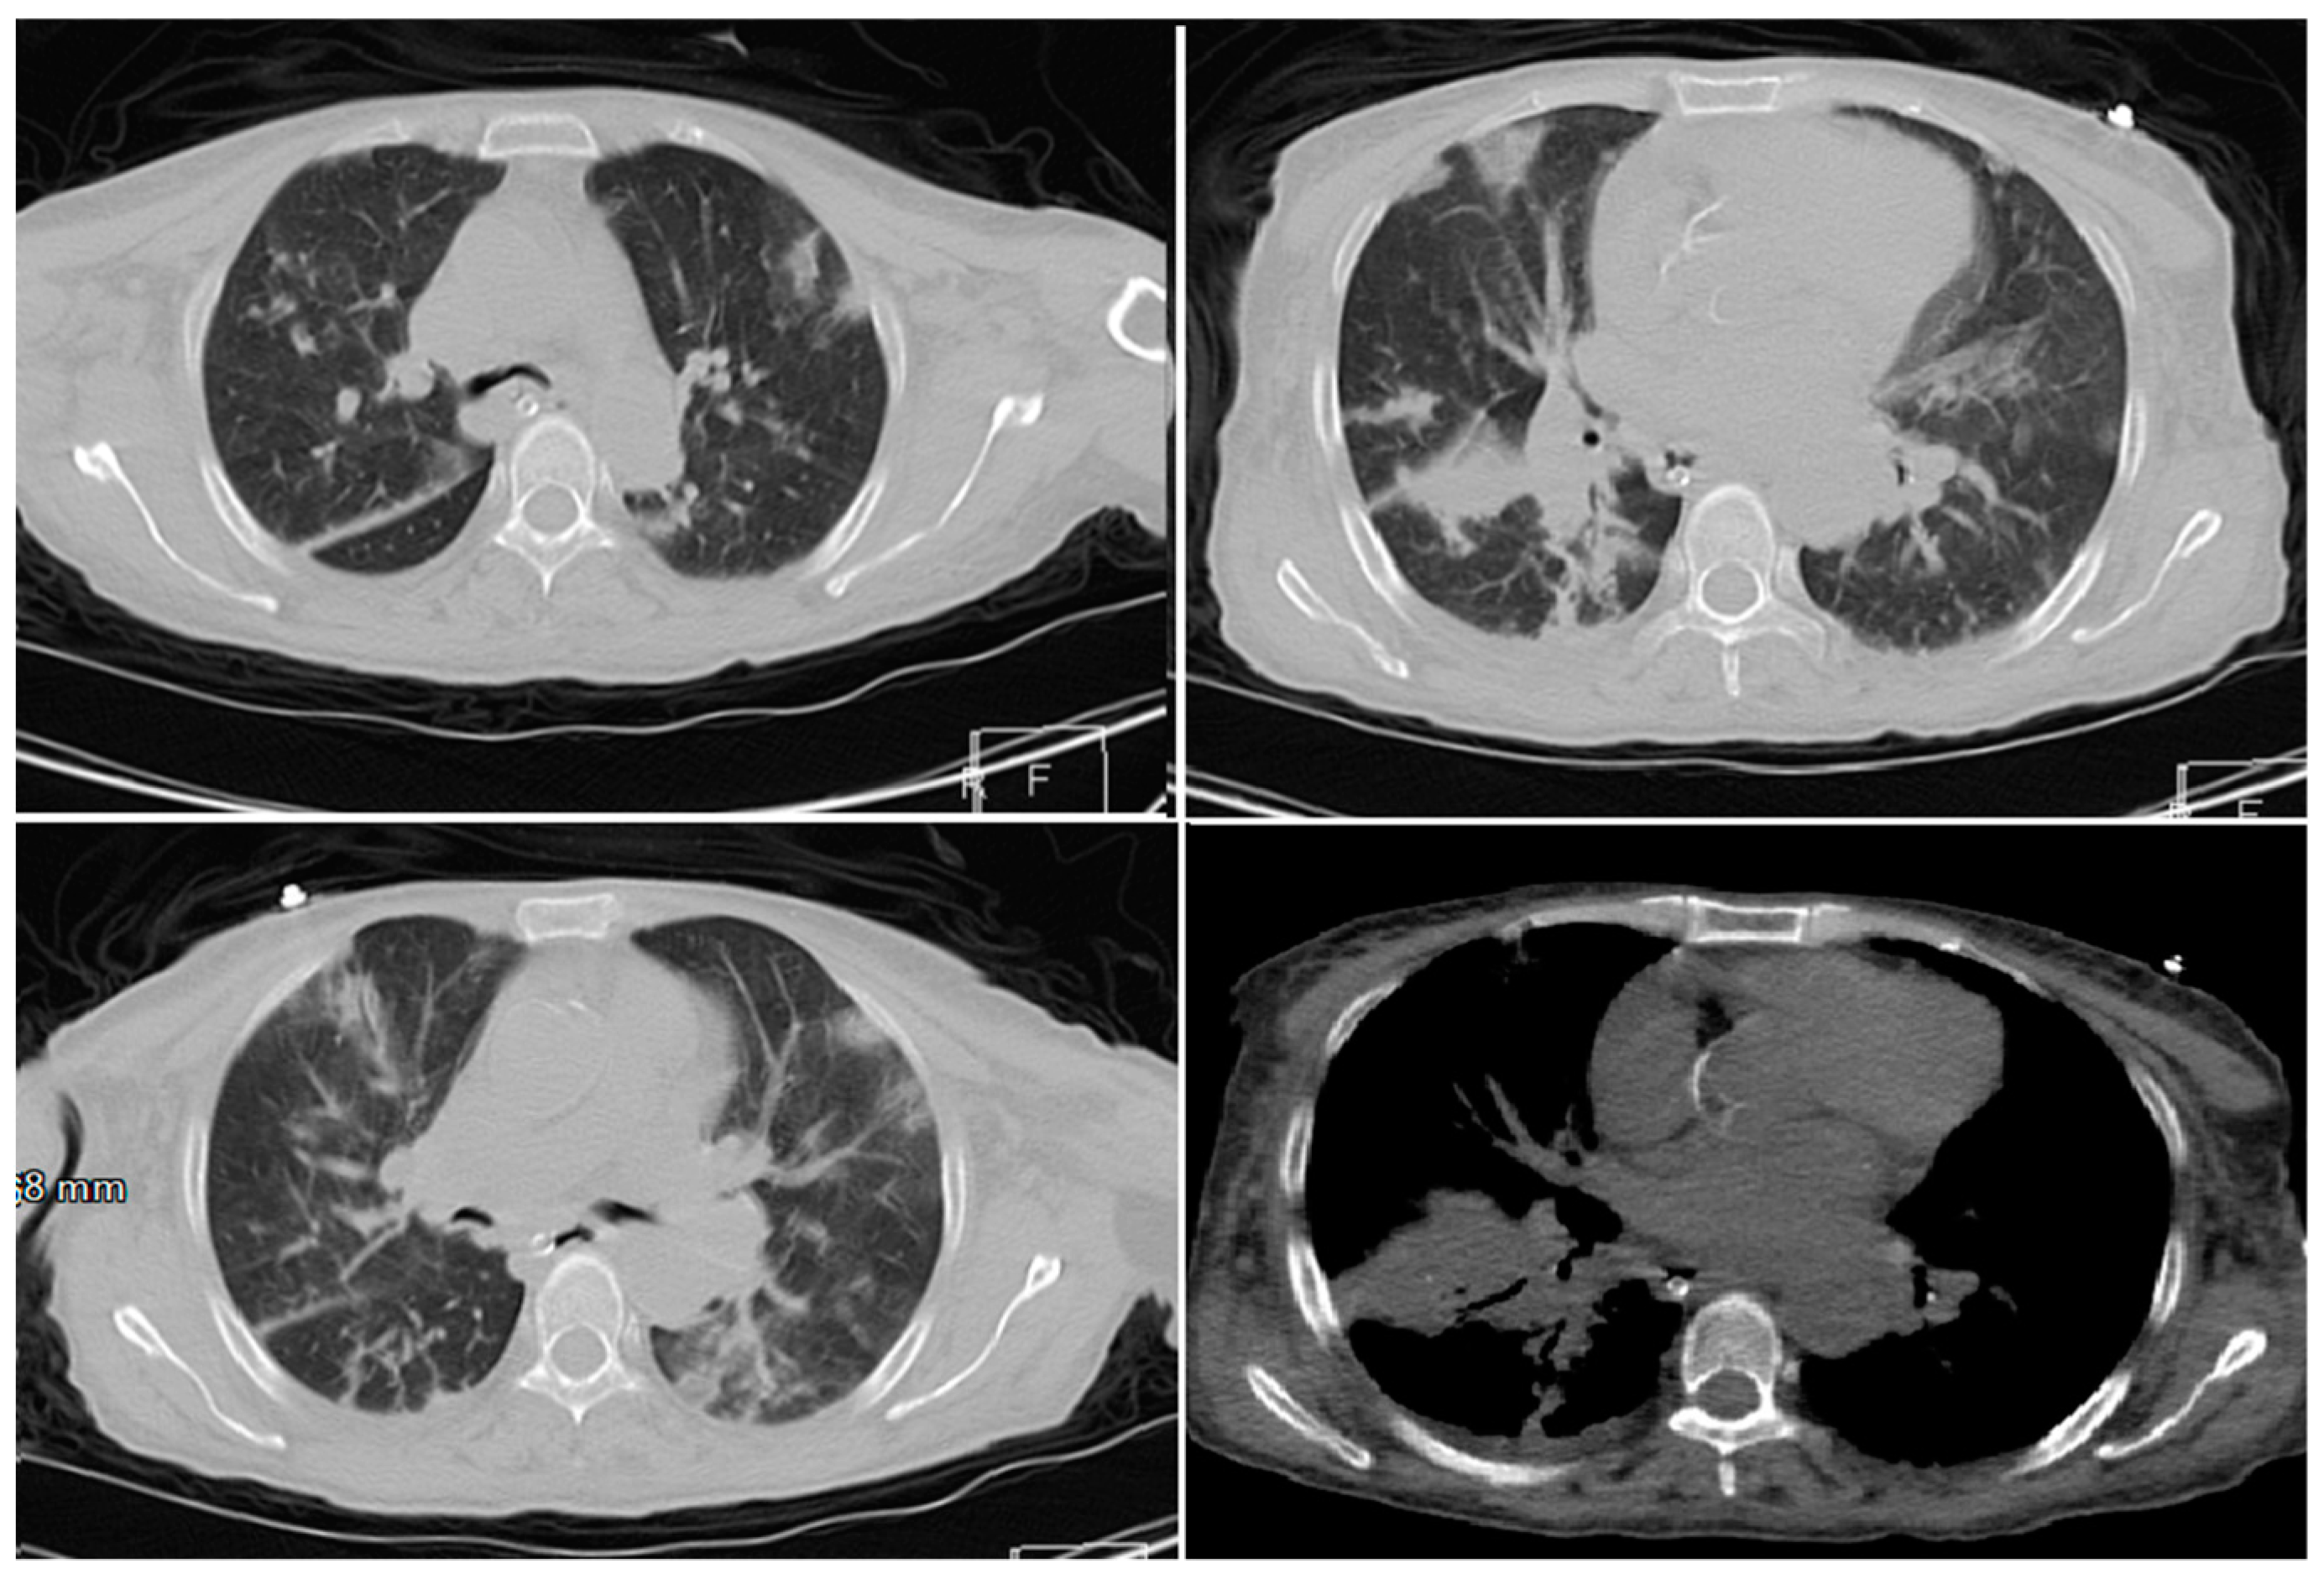

- Mahdavi, A.; Khalili, N.; Davarpanah, A.H.; Faghihi, T.; Mahdavi, A.; Haseli, S.; Sabri, A.; Kahkouee, S.; Kazemi, M.A.; Mehrian, P.; et al. Radiologic Management of COVID-19: Preliminary Experience of the Iranian Society of Radiology COVID-19 Consultant Group (ISRCC). Iran. J. Radiol. 2020. [Google Scholar] [CrossRef]

- Pan, Y.; Guan, H. Imaging changes in patients with 2019-nCov. Eur. Radiol. 2020. [Google Scholar] [CrossRef]

- Ng, M.-Y.; Lee, E.Y.P.; Yang, J.; Yang, F.; Li, X.; Wang, H.; Lui, M.M.-S.; Lo, C.S.-Y.; Leung, B.; Khong, P.-L.; et al. Imaging Profile of the COVID-19 Infection: Radiologic Findings and Literature Review. Radiol. Cardiothorac. Imaging 2020. [Google Scholar] [CrossRef]

- Zu, Z.Y.; Jiang, M.D.; Xu, P.P.; Chen, W.; Ni, Q.Q.; Lu, G.M.; Zhang, L.J. Coronavirus Disease 2019 (COVID-19): A Perspective from China. Radiology 2020. [Google Scholar] [CrossRef]